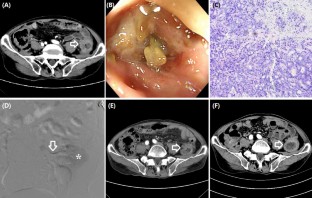

Fig. 1